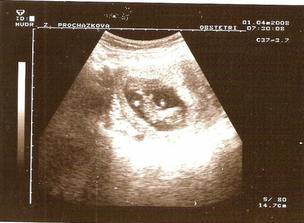

1.4.2008 - mimísek má CELÝCH 3,5 CM!!! :O)